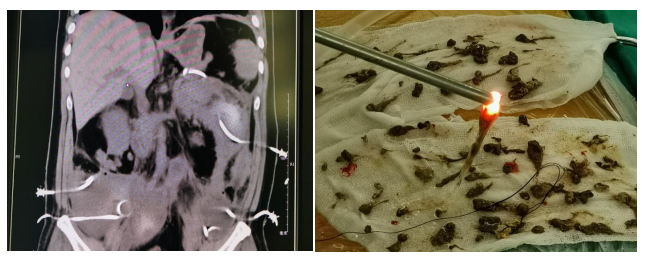

(Left) Wide ranging retroperitoneal necrosis and infection (Right) Necrotic tissue removed through nephroscopy

The peri-pancreas necrotic tissue debridement technique established in this study is of great significance for the treatment of necrotizing pancreatitis with locoregional infection. This technique enriches the therapeutic alternatives for necrotizing pancreatitis, validates the effectiveness of step-up treatment, and provides valuable reference in the treatment of intractable wide-range retroperitoneal necrosis and infection. In comparison with similar studies in the world, this study included more complex cases with a higher rate of 54.9% but resulted in a lower mortality rate (6.1%). "The new technique established in this study conforms to the concept of precision surgery, which is safe, minimally invasive and highly efficient. This technique deserves wide promotion to benefit more patients suffering from severe pancreatitis." Says Prof. Jiahong Dong, leader of this team, academician of Chinese Academy of Engineering.(Reviewer Jiang Liu)